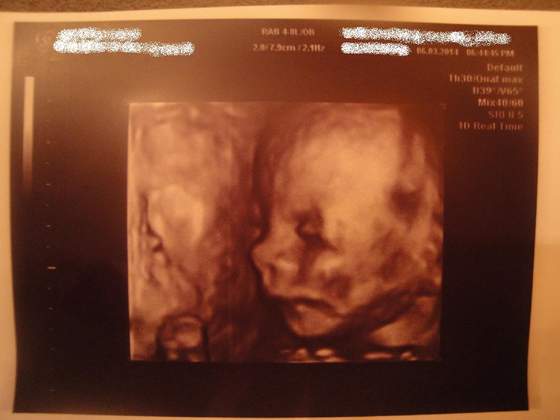

1400 mego Szczęścia

Zobacz załącznik 610714Zobacz załącznik 610715Zobacz załącznik 610716